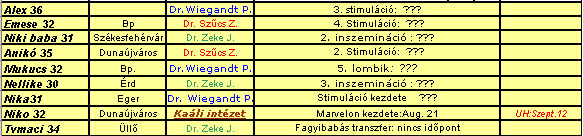

No, az új adatokat beírtam a táblába, már csak sorba rakok mindenkit, és dobok egyet!